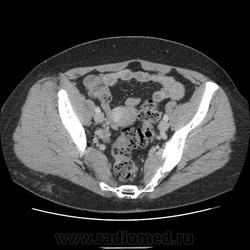

Женщина 50 лет, жалобы на тянущие боли в области малого таза, менопауза 1год, патологических выделений из влагалища не отмечает. На УЗИ киста правого яичника, левый яичник нормальный, объемное образование кишечника(?). На МРТ кистозно-солидное образование левого яичника, кишечника(?). Рекомендуют КТ. Как отдифференцировать? Киста справа понятно, слева то ли в яичнике, то ли... не было бы УЗИ и МРТ подумал бы на лейомиому матки. В понедельник будет делать ирригоскопию.